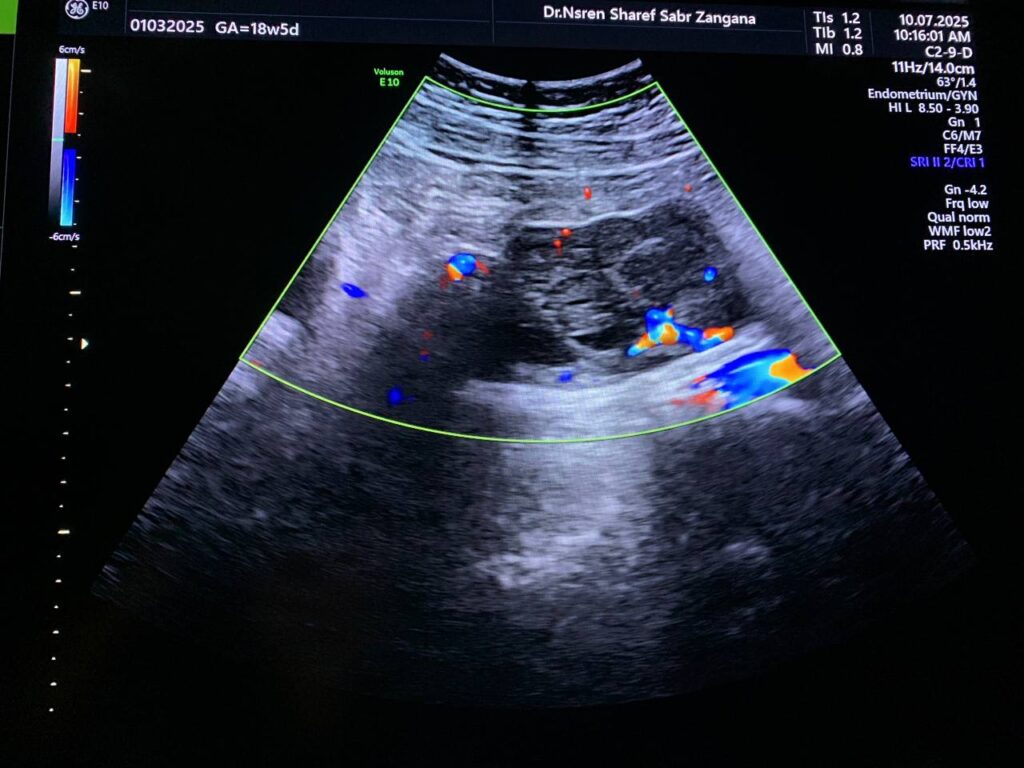

Pelvic Ultrasound

· Left ovarian solid mass vascular on color doppler score 2-3 , its size 57x48mm, no ascites , no enlarged lymph node seen, picture mostly ovarian tumor , please for further study.